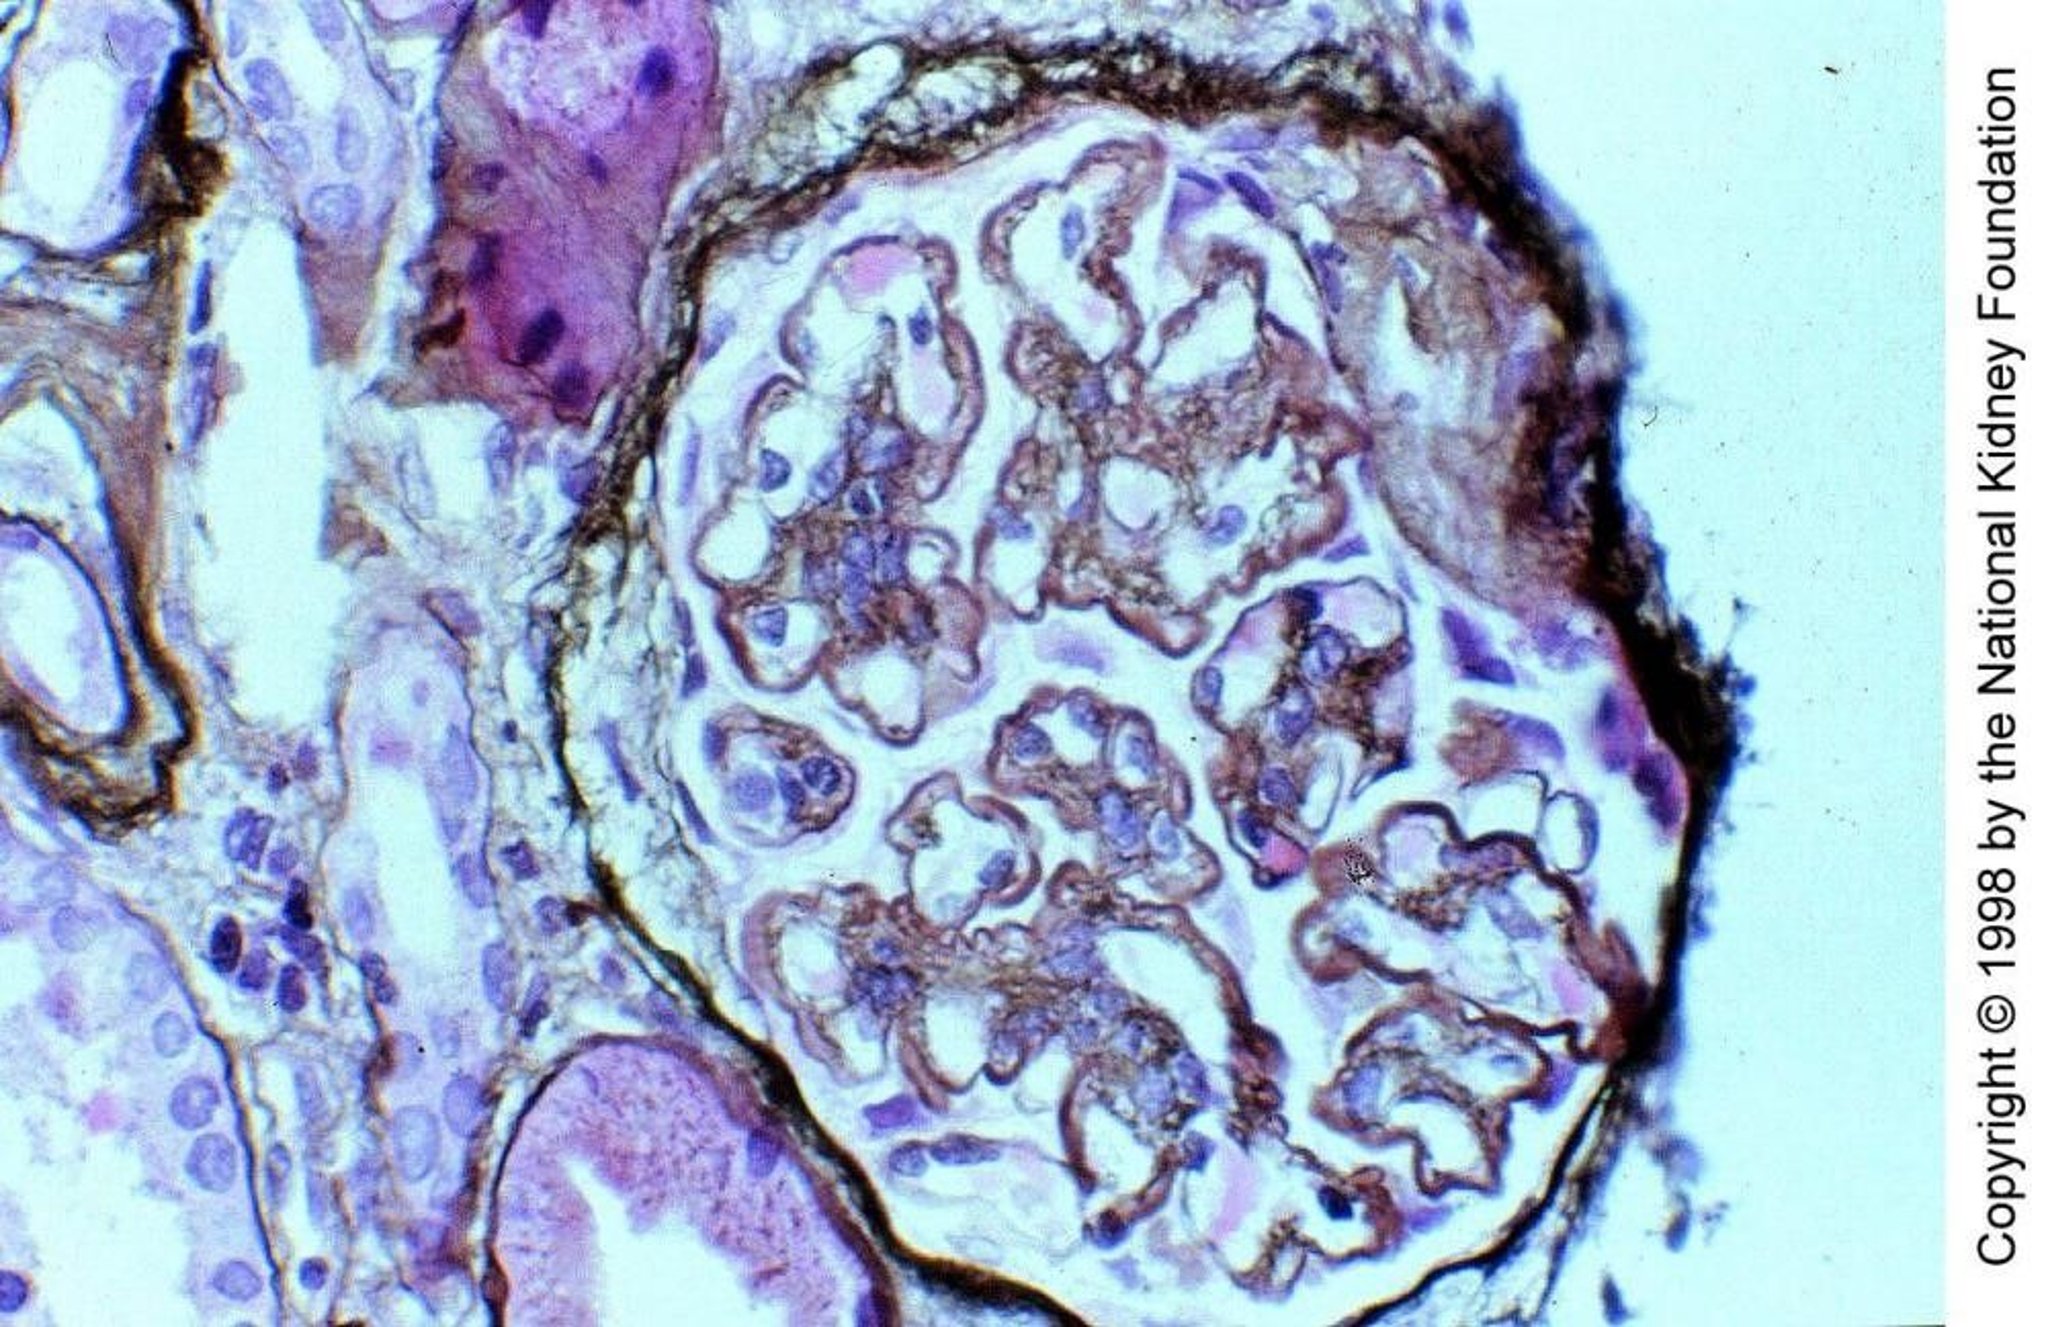

In complement-mediated membranoproliferative glomerulonephritis (MPGN) type II, C3 nephritic factor, an IgG autoantibody which functions like properdin by directly cleaving C3 to C3b, activates complement via the alternative pathway within glomerular capillary walls and mesangium. C3 deposits partially replace the basement membrane lamina densa, giving it a thickened and distinctive ribbon appearance (Jones silver stain, ×400).

Image provided by Agnes Fogo, MD, and the American Journal of Kidney Diseases' Atlas of Renal Pathology (see www.ajkd.org).